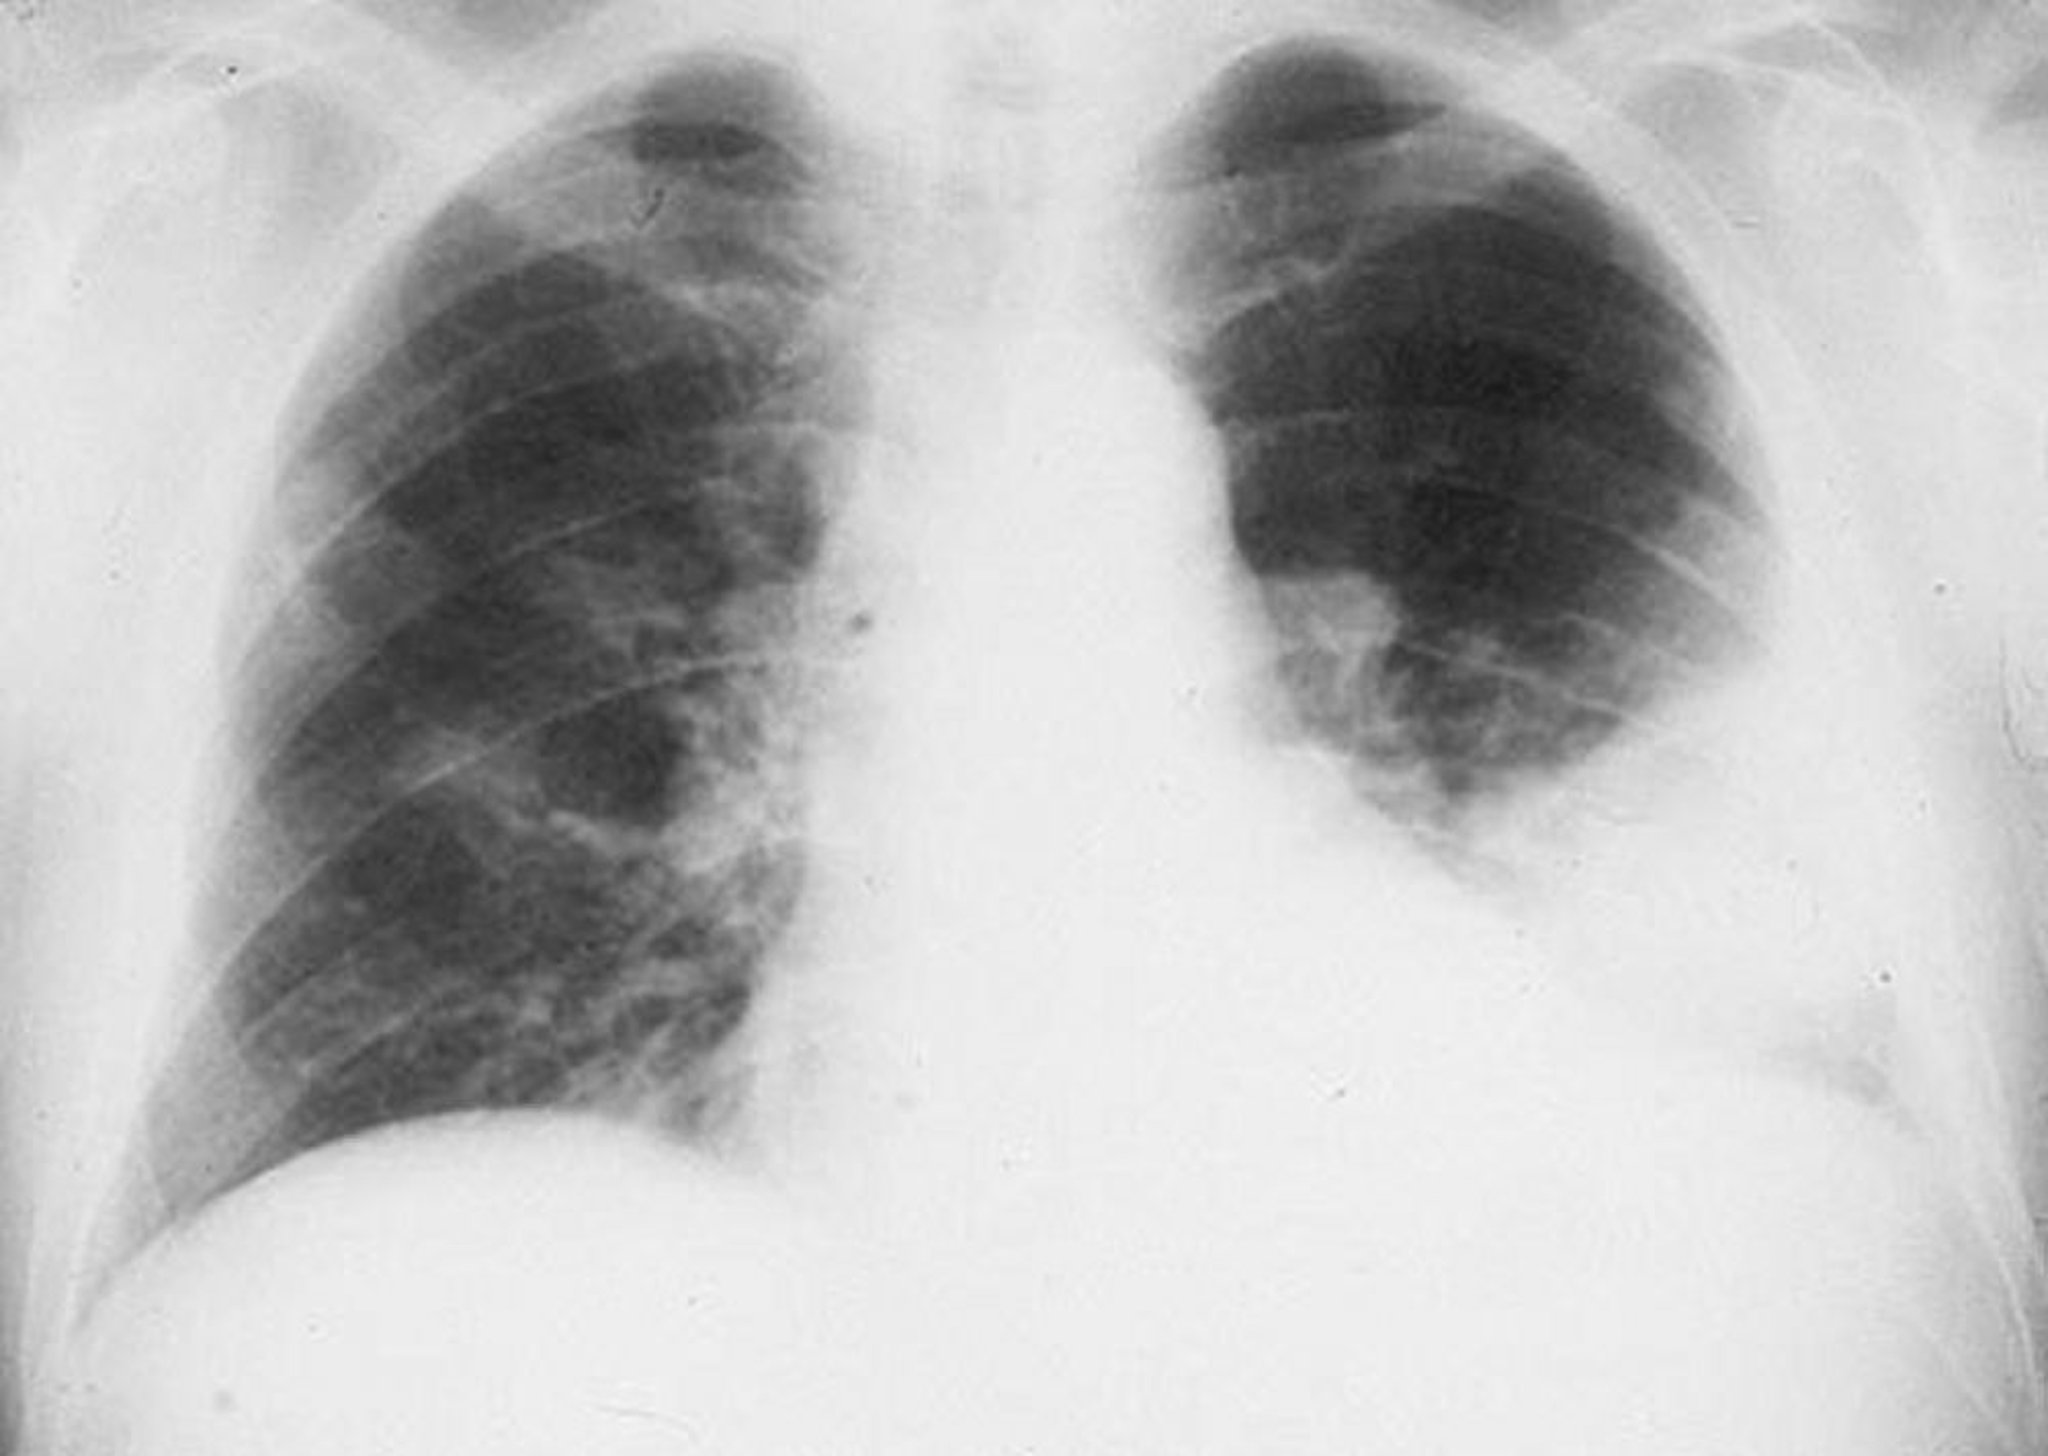

Инфильтрат нижней доли левого легкого

Альвеолярный инфильтрат в нижней доле левого легкого у пациента с бактериальной пневмонией.

By permission of the publisher. Из Roberts R. In Atlas of Infectious Diseases: Pleuropulmonary and Bronchial Infections. Edited by GL Mandell (series editor) and MS Simberkoff. Philadelphia, Current Medicine, 1996.